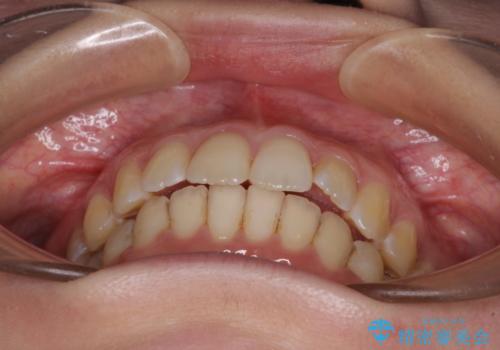

前歯のデコボコを解消 インビザラインによる矯正治療

- 上下前歯のデコボコと深い咬み合わせを気にして来院された患者様です。

インビザラインによる上下歯列の拡大と、IPR(歯と歯の間を削る)にるスペースの獲得により、前歯のデコボコを改善することとしました。

上の前歯をもう少し整えたかったのですが、患者様の治療を早く終了させたいという希望により、細かい叢生を残しての終了となりました。